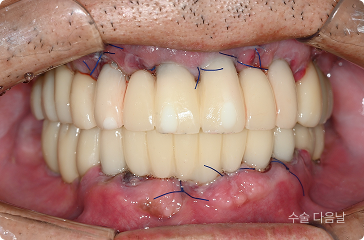

60세, 남 ㅣ중요한 일정 전

“딸이 곧 결혼하는데 그 전에 빨리 치료를 끝내고 싶어요.”

치료 전

원데이 임플란트

치료 후

• 6개월 후 딸의 결혼식 등 중요한 일정 앞둔 상태

• 의식하진정(수면마취) 하 전체 발치,

임플란트 수술 후 원데이 예비 치아 장착

• 발치 , 임플란트 식립 > 최종 보철

약 4개월 내 완성